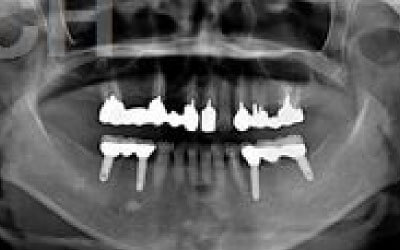

CTを使うことで、骨や歯の状態を3Dで確認でき、正確な距離測定も行えます。

骨の厚さや傾き、神経の位置などを事前にしっかりと計測することで、安全にインプラント治療を行うことができます。